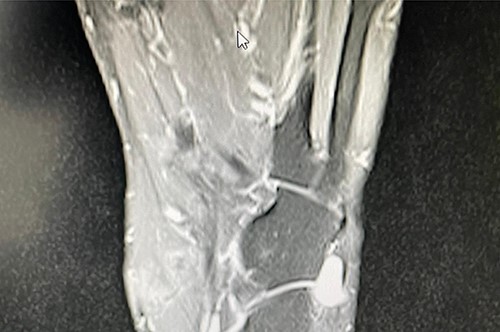

A 50-year-old lady presented to us with a lump in her left foot on the lateral aspect at the level of the calcaneocuboid joint for a 1-year duration, which was associated with pain. She consulted her GP who advised an US scan. This revealed a lump over the dorsum of the left foot on the lateral side. She also had a magnetic resonance imaging (MRI) scan which was indeterminate (Figs 3 and 4). It was reported as a suspected sarcoma. She was then referred to the Sheffield sarcoma unit where she underwent a biopsy of the swelling; which was reported as angiomyolipoma (a benign swelling). She was not keen on excision initially, but as the swelling increased in size and started becoming painful, she underwent an excision of the lesion under our care and the histopathologic examination of the excised sample confirmed it to be angioleiomyoma. The post-operative period was uneventful and she was discharged from our care after 10 weeks. At this time, she was symptom-free and had a pain score of 0/10.

T2 axial MRI image of the soft tissue lesion over the lateral foot in Patient 2 showing a lesion which is heterogeneous and slightly hyperintense to the muscle.

Similarly, in Case 2, the patient had an MRI scan which reported an indeterminate swelling suggestive of a possible sarcoma. As the MRI findings were not characteristic of the MRI findings of an angioleiomyoma, such as T1: isointense or hyperintense to muscle, T2: heterogeneous and slightly hyperintense to muscle and T1 C+ (Gd): homogenous to heterogeneous enhancement, suspicion of the sarcoma was reported from the MRI scan findings and referral to sarcoma unit was advised. This clearly shows that the US and the MRI scan findings can suggest a different diagnosis, and a confirmed diagnosis was only established following excision and histopathological examination of the excised lesion. Usually, angioleiomyomas have a peripheral low-intensity signal rim corresponding to a fibrous pseudo capsule with adjacent vascular structures with isointense or hypointense to muscle on T1 images and heterogeneous and slightly hyperintense to muscle on T2 images.